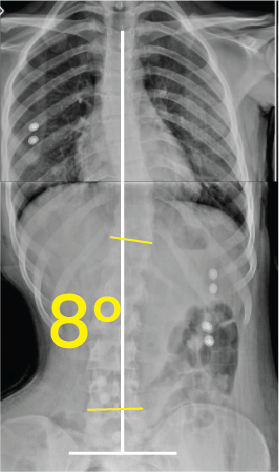

Omurga eğriliğini ve 30 derece açıyı gösteren iskeletin göğüs-karın röntgeni.Göğüs ve karın bölgesinin iki farklı açıyla çekilmiş röntgen görüntüsü ve üzerinde 8 derece açı gösteren sarı işaret.